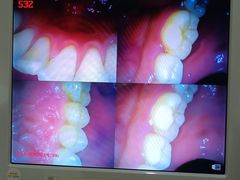

• 土豆口腔(凤凰北总店)

• -土豆口腔(凤凰北总店)

金文博_5274 | 24-11-01